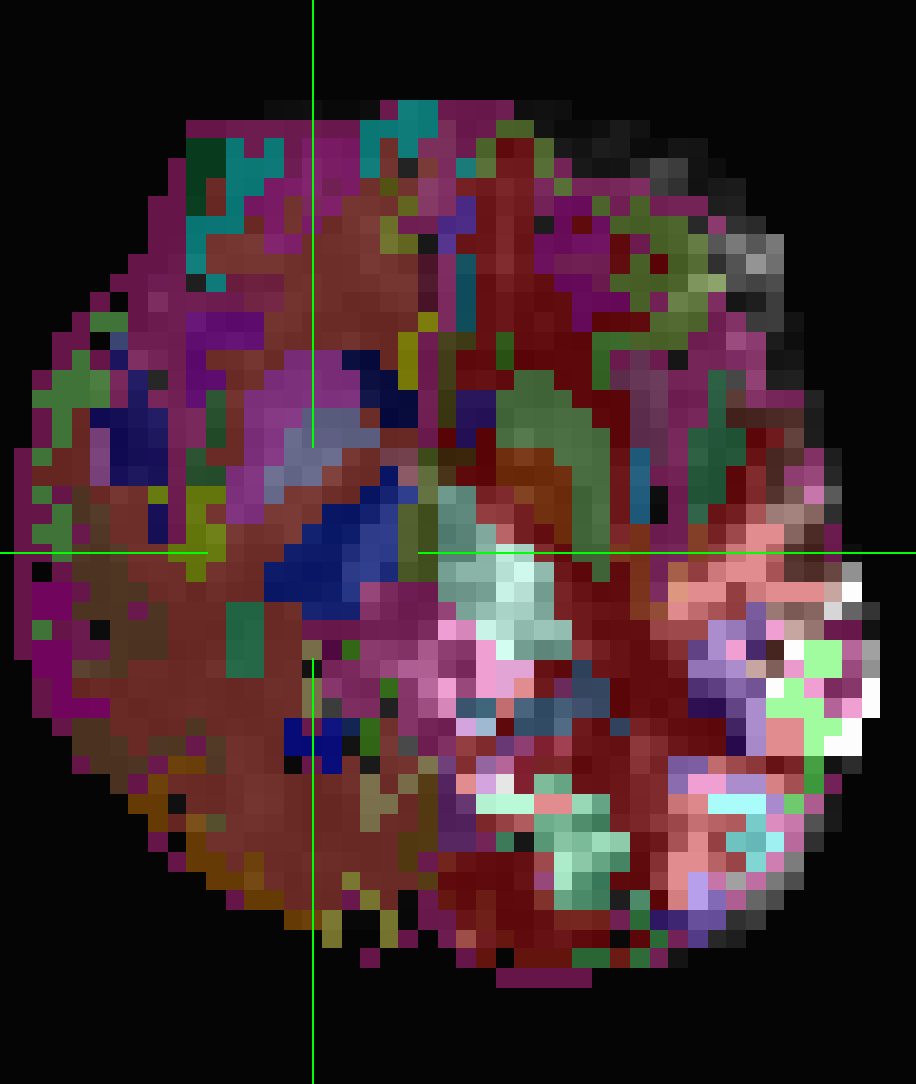

The follow_ROI_FS_REN_epi which was resampled on epi after volreg is also not aligned with anatSS when viewing in AFNI

Same when I overlay follow_ROI_FS_REN_epi on pb02_sub-ep069.r01.volreg

When I overlay follow_ROI_FS_REN_epi on stats.sub-ep069_REML+orig.BRIK.gz they are off, but there is no oblique